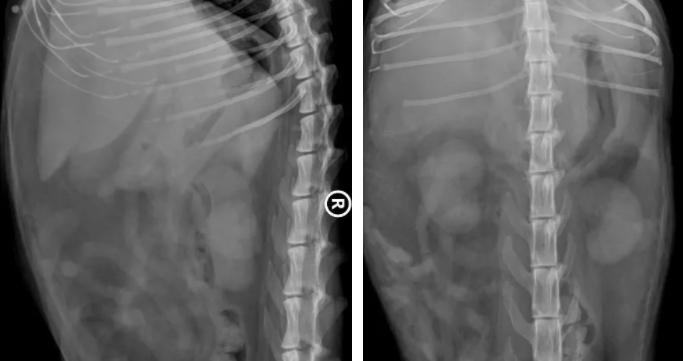

影像学检查:超声检查可发现弥散性高回声的肝脏。且肝脏不同程度肿大